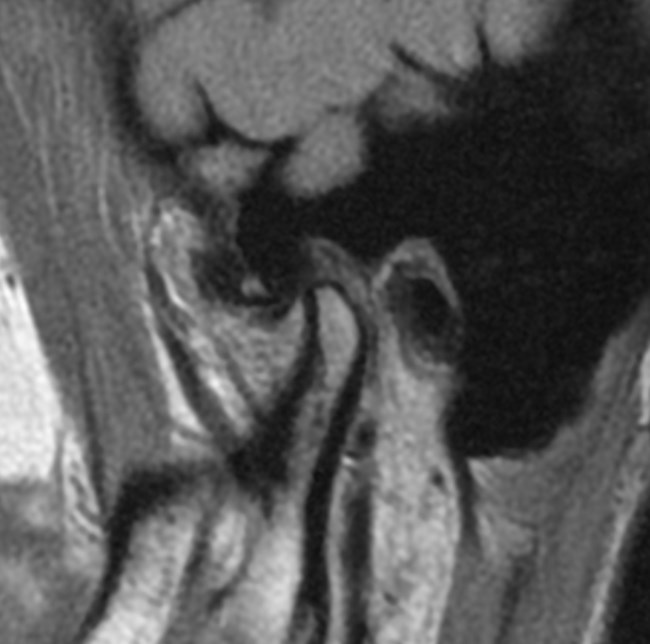

Na podstawie uzyskanych wyników badań zastosowano repozycyjną szynę zgryzową oraz terapię manualną narządu żucia. Po trzymiesięcznym leczeniu uzyskano poprawę modelu ruchomości żuchwy. W związku z utrzymywaniem się silnych dolegliwości bólowych zlecono dodatkowo badanie tomografii rezonansu magnetycznego (MR), w którym w zwarciu stwierdzono obustronne doprzednie przemieszczenie krążków stawowych (ryc. 5). W zwarciu na przekrojach czołowych widoczne było spłaszczenie powierzchni stawowej lewego ssż (ryc. 6). W rozwarciu pozycja obydwu głów żuchwy była doprzednia w stosunku do szczytów guzków stawowych, a nad głowami żuchwy leżały pasma przednie krążków stawowych. Przemieszczenie głowy żuchwy było bardziej nasilone w prawym stawie skroniowo-żuchwowym (ryc. 7).

Ryc. 5a i 5b. Przekroje strzałkowe MR ssż w zwarciu, obrazy PD-zależne. Doprzednie przemieszczenie krążków w prawym (a) i lewym (b) ssż.

Ryc. 6a i 6b. Przekroje czołowe MR ssż w zwarciu, obrazy PD-zależne. Widoczne spłaszczenie powierzchni stawowej lewego ssż.

Ryc. 7a i 7b. Przekroje strzałkowe MR ssż w rozwarciu, obrazy PD-zależne. Doprzednie położenie głów żuchwy w obydwu ssż, nad głowami żuchwy widoczne pasma przednie krążków stawowych.